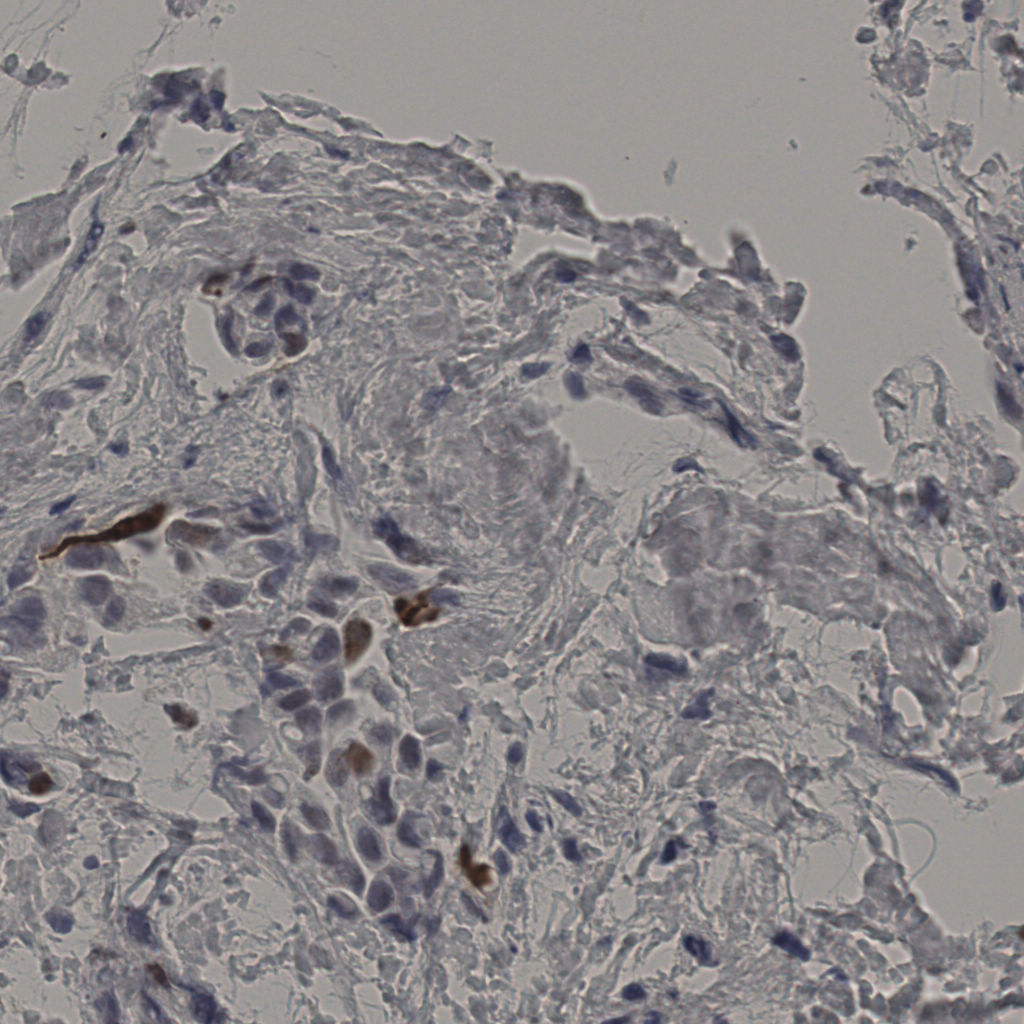

slice_31_5_x27776...

slice_31_6_x27776...

slice_31_7_x27776...

slice_31_8_x27776...

slice_31_9_x27776...

slice_32_10_x2867...

slice_32_11_x2867...